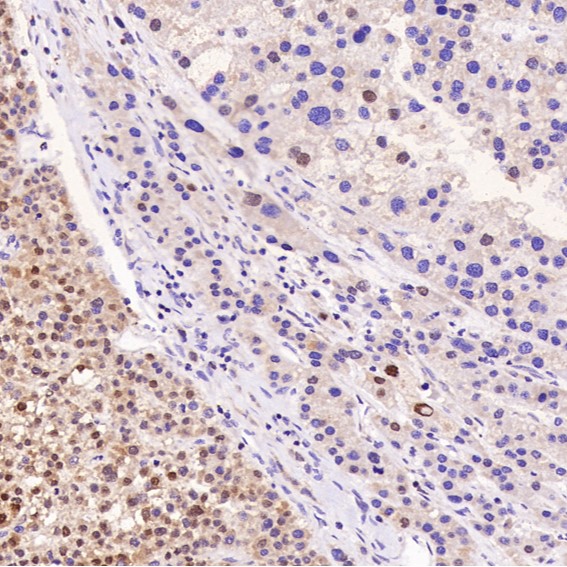

Immunohistochemical analysis of paraffin-embedded Human liver cancer, using the Antibody at 1:200 dilution.

Immunohistochemical analysis of paraffin-embedded human liver cancer, using Bcl-XL Antibody.